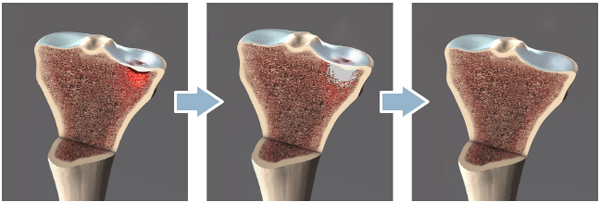

The Subchondroplasty™ procedure is a minimally invasive surgery designed to treat subchondral defects associated with chronic bone marrow edema (BME) by filling them with a hard-setting, biomimetic bone void filler.

Chronic BME is a defect of the bone typically 0-10 mm below the cartilage. Chronic BME is characterized by an area of inflamed edema surrounding micro fractures or defects. Many surgeons believe that chronic BME will not heal without treatment.

During the procedure, your surgeon will use a guide instrument to access the subchondral defect and fill it with a bone substitute to allow new, healthy bone to repair the defect.